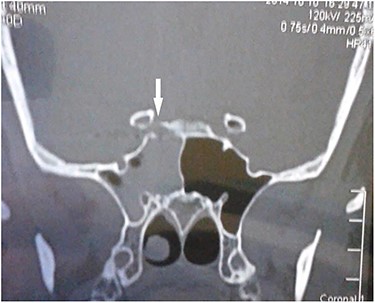

Computed tomography (CT) of the paranasal sinuses and angiography were requested on an urgent basis, which confirmed a diagnosis of pseudoaneurysm in her right CCA, adjacent to retained pellets (Figs 1–4). Also, her hemoglobin dropped from 11.5 to 8.4 gm over a 6-month period. Afterwards, she was referred to the interventional radiology department. She underwent stenting and coiling of her right internal carotid artery after which no further epistaxis happened for an uneventful year of follow-up.

Carotid angiography showing small gun pellets (yellow arrows) and pseudoaneurysm (red arrow) of the right CCA.